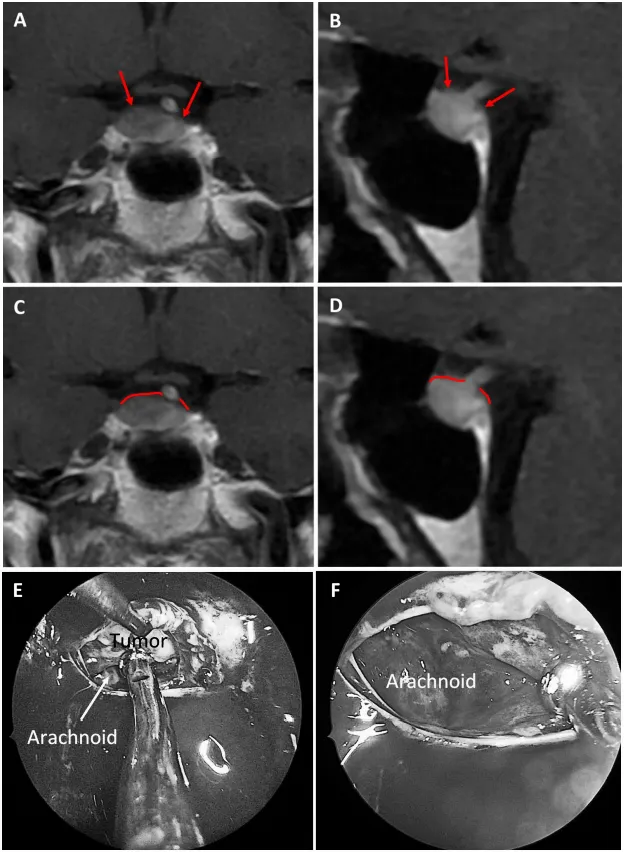

图6:59岁女性泌乳素腺瘤患者。a、b术前MRI:红色箭头指示厚度小于1毫米的强化屏障区。c、d术前MRI:红色标记线标示薄弱屏障位置。e、f术中图像:可见由蛛网膜构成的屏障结构。

图7:69岁女性生长激素腺瘤患者。a、b术前MRI:黄色箭头指示厚度小于1毫米的强化屏障区。c、d术前MRI:红色标记线标示薄弱屏障位置。e、f术中图像:可见由蛛网膜构成的屏障结构。